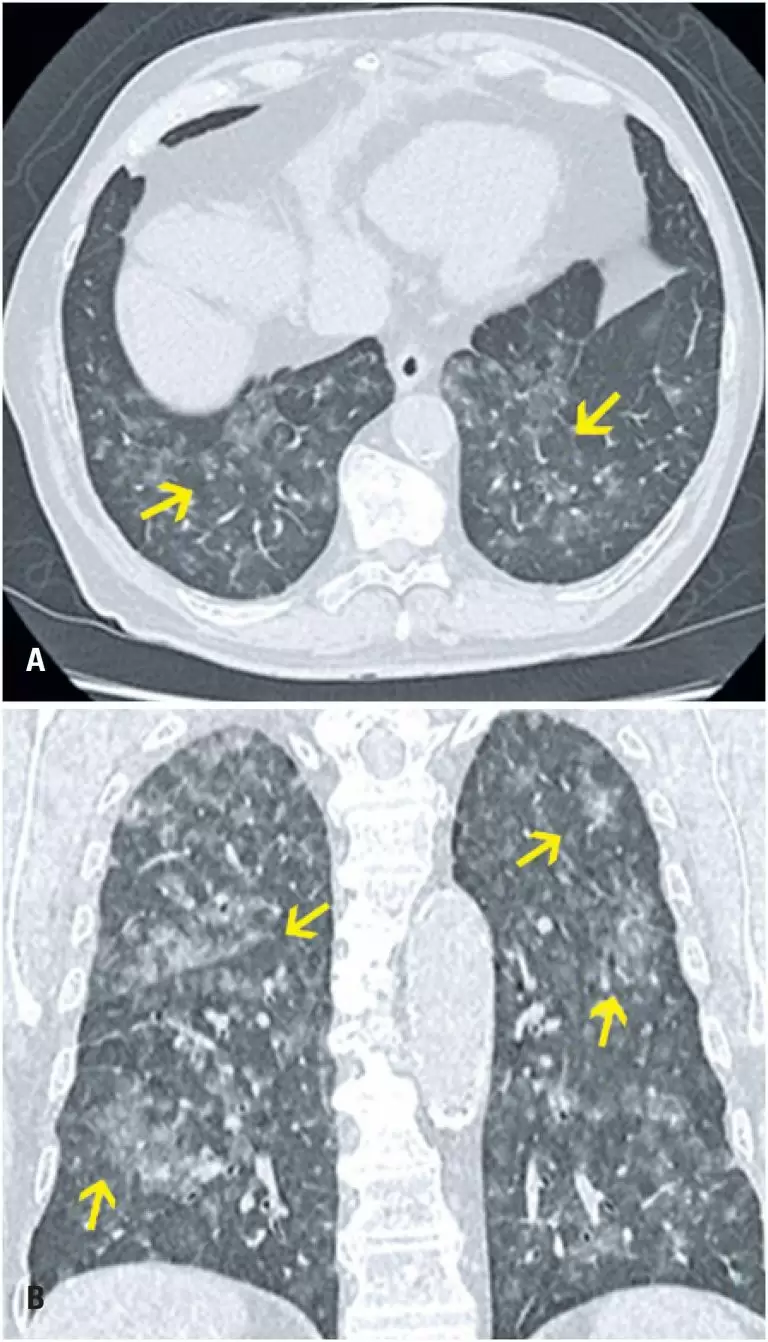

Diagnósticos diferenciais de opacidade em vidro fosco aguda na tomografia computadorizada de tórax: ensaio pictórico

DOI: 10.31744/einstein_journal/2021RW5772

RESUMO A opacidade em vidro fosco é uma alteração muito frequente e pouco específica na tomografia computadorizada de tórax. Ela admite grande leque de diagnósticos diferenciais no contexto agudo, desde pneumonias virais, como as causadas pelo vírus influenza, pela doença do coronavírus 2019 e pelo citomegalovírus, até mesmo lesões de origem não infecciosa, como vaping , infarto pulmonar, hemorragia alveolar e edema pulmonar. Para essa diferenciação diagnóstica, deve-se correlacionar o vidro fosco com os demais achados nos exames de imagem, […]

Palavras-chave: COVID-19; Diagnóstico diferencial; Infecções por coronavírus; Pandemia; SARS-CoV-2; Tomografia computadorizada por raios X; Tórax/diagnóstico por imagem